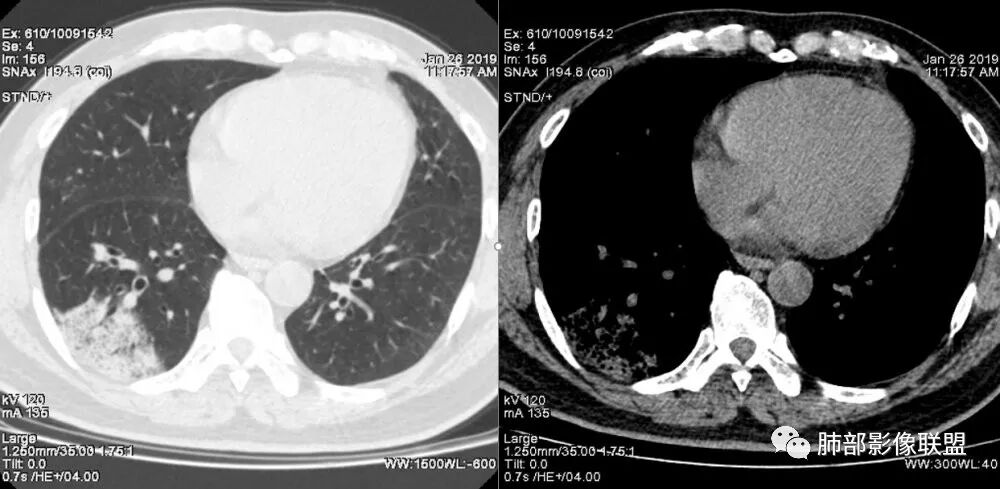

老年女性,右肺下叶沿胸膜下大片状高密度影,外周磨玻璃影,边界较清,内可见蜂窝征及支气管充气征,考虑肺炎型肺癌。

老年女性,咳嗽咳痰病史,右肺下叶大片磨玻璃实变影,胸膜下分布,支气管进入后扩张、僵直,磨玻璃影边界清楚,考虑粘液腺癌。鉴别肺炎。

中年女性,咳嗽咳痰。右肺下叶片状高密度影,部分实性密度,周围见边界清晰磨玻璃影,内见小空泡,实性区部分支气管堵塞,有重力效应,考虑肺炎型肺癌,建议查痰脱落细胞。

患者中年女性,咳嗽咳痰就诊。胸部CT:右肺下叶后基底段片状实变影,由胸膜向内发展呈扇形,病灶里有小叶内间质增厚、蜂窝状影,周围边界清楚GGO,内可见扩张支气管,淋巴结无明显肿大。综合符合粘液腺癌。

老年女性,咳嗽、咳痰。右肺下叶沿胸膜下大片状高密度影,外周磨玻璃影,边界较清,小空泡,蜂窝征及支气管充气征,叶间裂串珠征,考虑:肺炎型肺癌,鉴别:肺克,链球菌,NTM等感染。

中年女性,右肺下叶实变,近似扇形,外朝内发展趋势,外围紧贴胸膜面,中心密度略高,边缘密度略低,病灶内支气管略扩张。考虑肺炎型肺癌。常规建议抗炎治疗后复查,如无变化或变化不明显,建议穿刺活检。

起源于胸膜下,实性成分,边缘Ggo,边界清晰,内可见小叶间隔增厚,粘液腺癌可能。建议先消炎后复查。

1.本例病灶较大片混杂密度影,胸膜下分布为主(未沿着支气管分布),该分布特点可见于大叶性肺炎、干酪性肺炎、淋巴瘤及粘液腺癌等。可惜未提供增强扫描图像。

2.病灶示中央实变区,周围GGO,可见明显小叶间隔增厚,GGO边界清楚,应当考虑到恶性病变的可能性。肺炎因炎性水肿及渗出,影像上边界常模糊不清,注意早期粘液腺癌可出现似清非清的边界。粘液腺癌因粘液成份较多,密度一般偏低,纵隔窗病灶常会消隐或范围会明显缩小,这不同于炎性实变。

3.病灶内支气管走形略显僵直,侧支少(粘液阻塞),也符合肺腺癌的枯树枝征。而大叶性肺炎的支气管是管壁光整、通畅、自然,结核的支气管常常壁增厚,甚至狭窄后扩张;

4.患者临床症状不重,临床炎性指标不高,结合肺内影像,应警惕肺炎型肺癌。